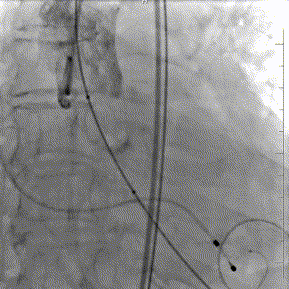

术中,通过预塑形导丝送入左室,主动脉根部造影反流,延大鞘进入输送系统,定位输送系统位置,瓣膜释放1/3时,起搏160bpm,快速释放至3/4处,瓣膜正常工作,手术顺利完成。

释放定位

最终结果